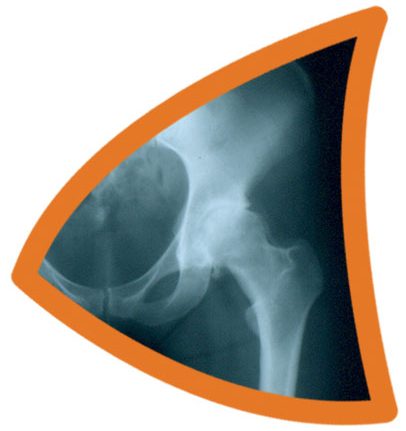

Hip Pain

Hip pain is not always felt directly over the hip. Instead, it may be felt in the thigh, groin or in the knee. Similarly, pain in the hip might be actually a sign of a problem in the back, rather than the hip itself.

Causes of Hip Pain

To direct appropriate treatment at the underlying problem, it is very important that the main causative factor of hip pain be diagnosed. Some of the more specific causes of hip pain can include: